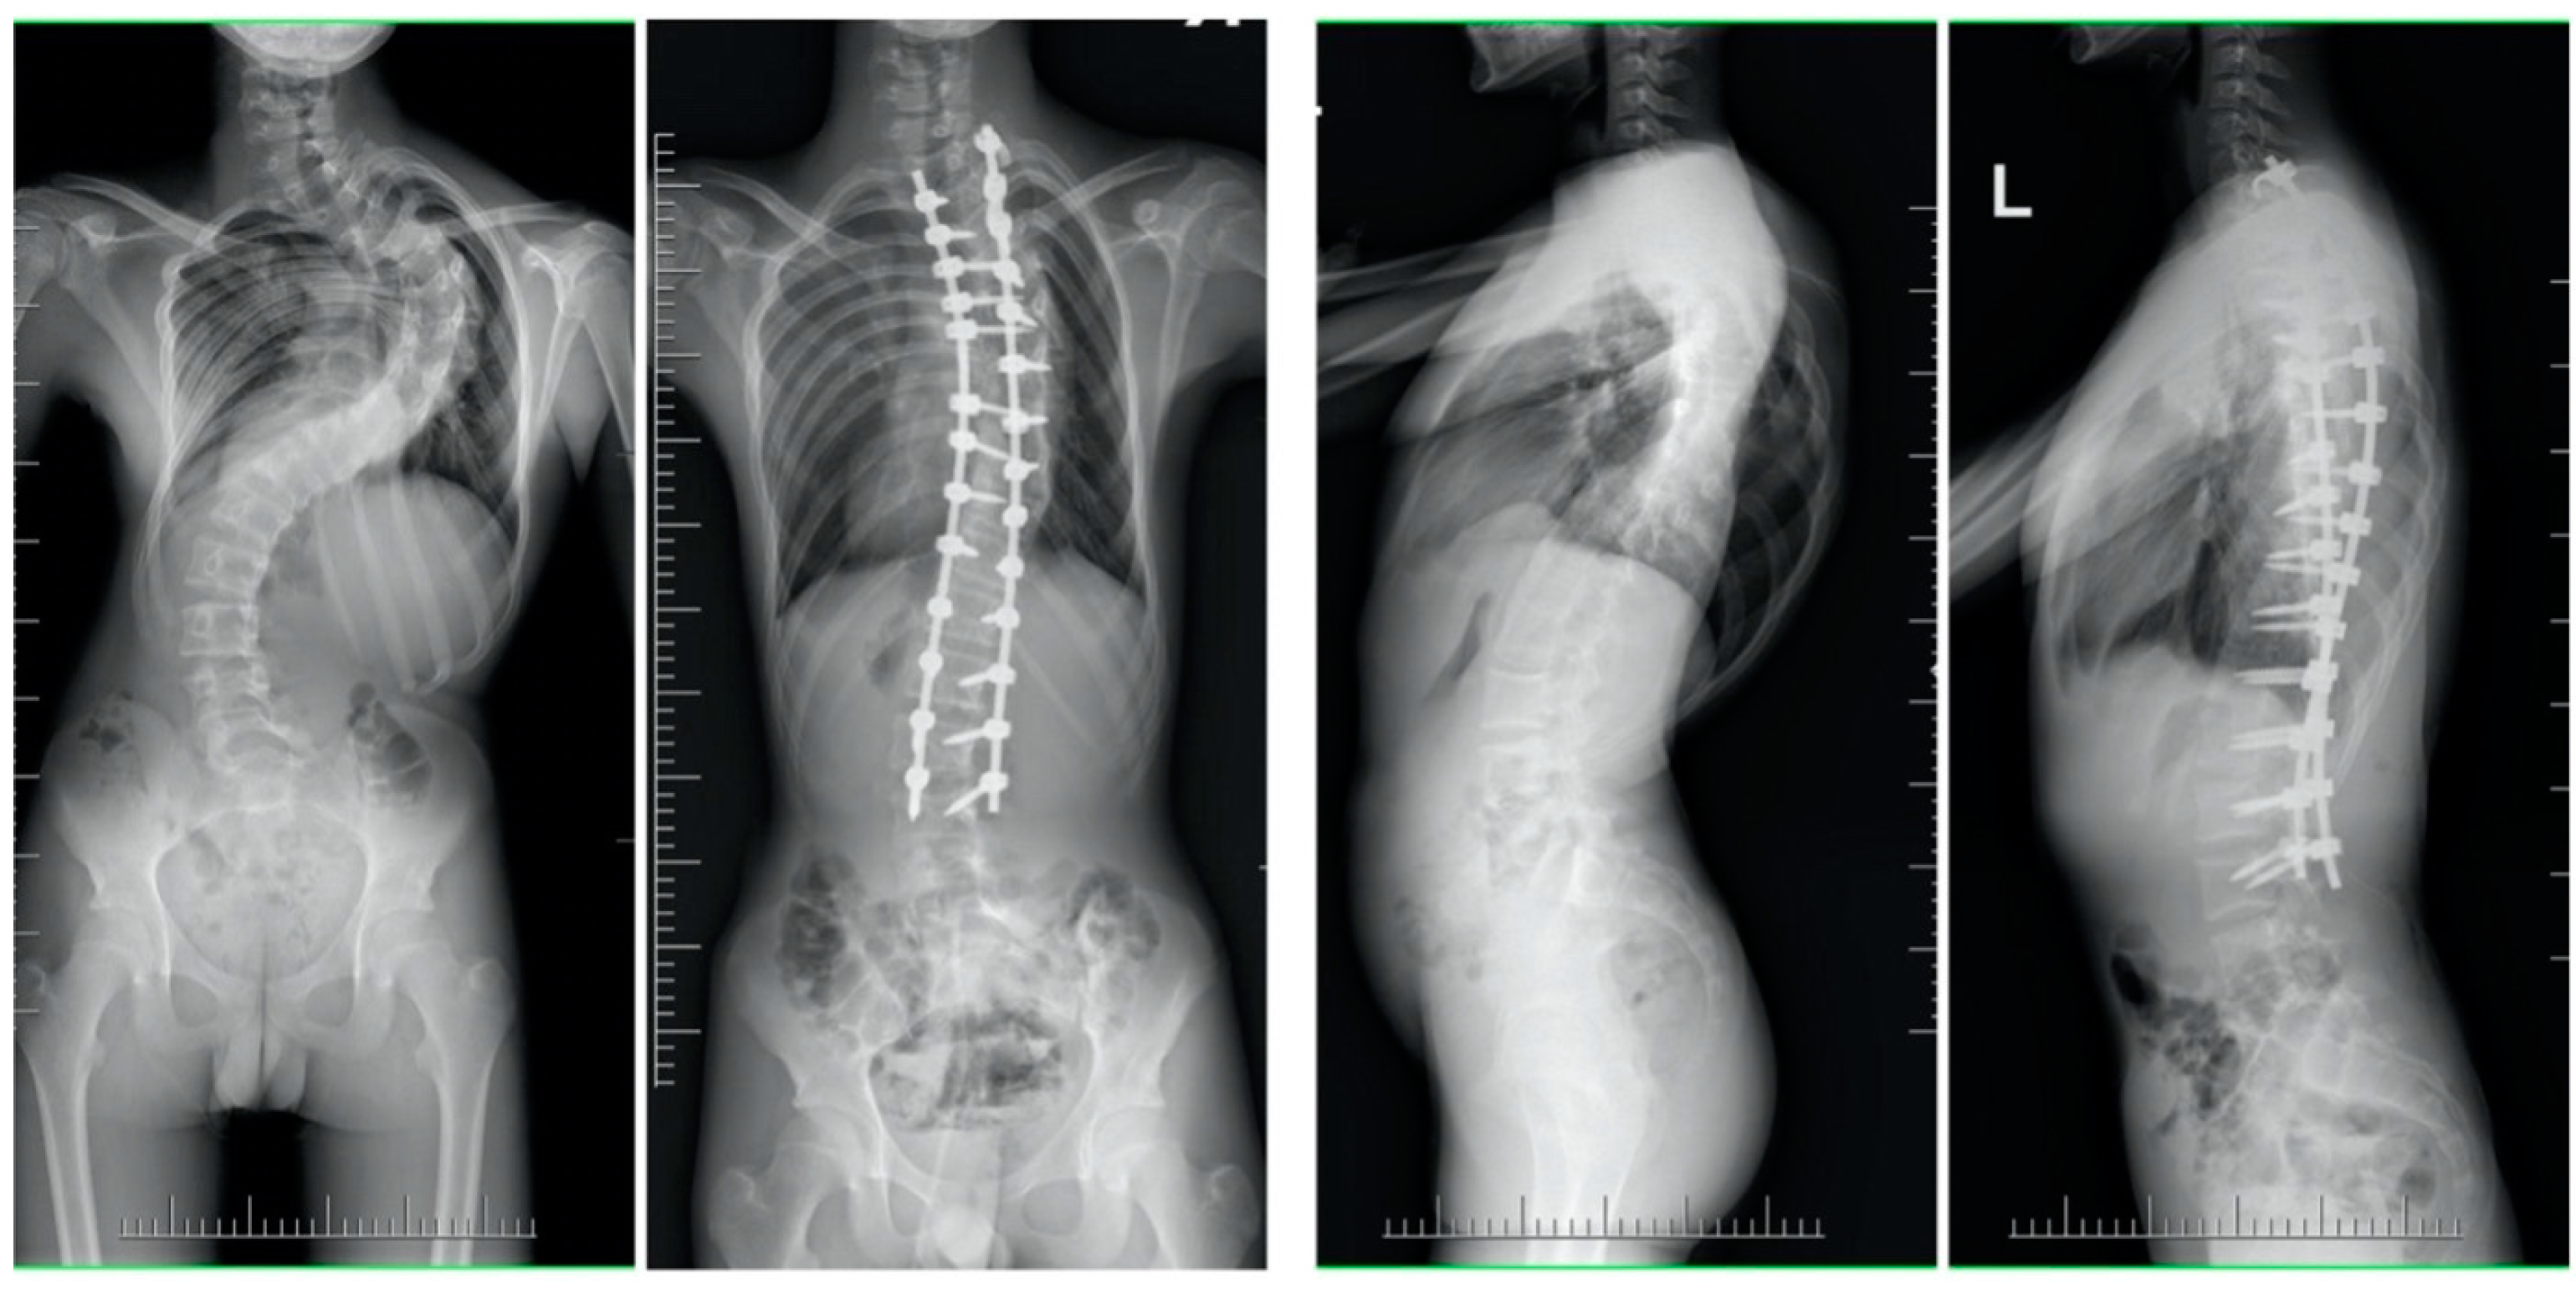

| Mean (SD) preoperative Cobb, deg | 131 (13.8) | 60 (9.5) | <0.001 |

| Mean (SD) Cobb at final follow-up, deg p-value * (pre vs. follow-up) | 61 (19.2) | 18 (9.2) | <0.001 |

| Mean (SD) preoperative thoracic kyphosis T5-T12, deg | 83 (35.9) | 25 (14.2) | <0.001 |

| Mean (SD) thoracic kyphosis T5-T12 at final follow-up, deg p-value * (pre vs. follow-up) | 35 (9.6) | 22 (8.2) | 0.24 |

| Mean (SD) preoperative apical vertebral translation, mm | 92 (32.4) | 65 (14.8) | <0.001 |

| Mean (SD) apical vertebral translation at final follow-up, mm p-value * (pre vs. follow-up) | 31 (9.8) | 22 (6.8) | 0.22 |